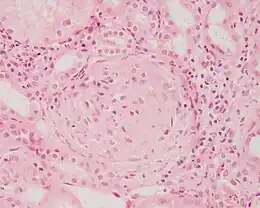

Description de l'image Crescentic glomerulonephritis HE stain.JPEG.

Une glomérulonéphrite est une affection (souvent d'origine inflammatoire) du glomérule, composante du néphron, l’unité fonctionnelle du rein. Ses manifestations affectent les deux reins de manière égale. Elle peut être asymptomatique, mais le plus souvent elle est responsable d'hématurie ou de protéinurie. La glomérulonéphrite peut être aigüe ou chronique. Les glomérulonéphrites sont le plus souvent primitives mais on peut parfois mettre en évidence des causes infectieuses (bactériennes, virales ou parasitaires), auto-immunes ou au syndrome paranéoplasique.

Le diagnostic se fait par biopsie rénale. Suivant les lésions, on parle de glomérulonéphrite extramembraneuse, de glomérulonéphrite membranoproliférative, de glomérulonéphrite segmentaire et focale de lésions glomérulaires minimes, de maladie de Berger.